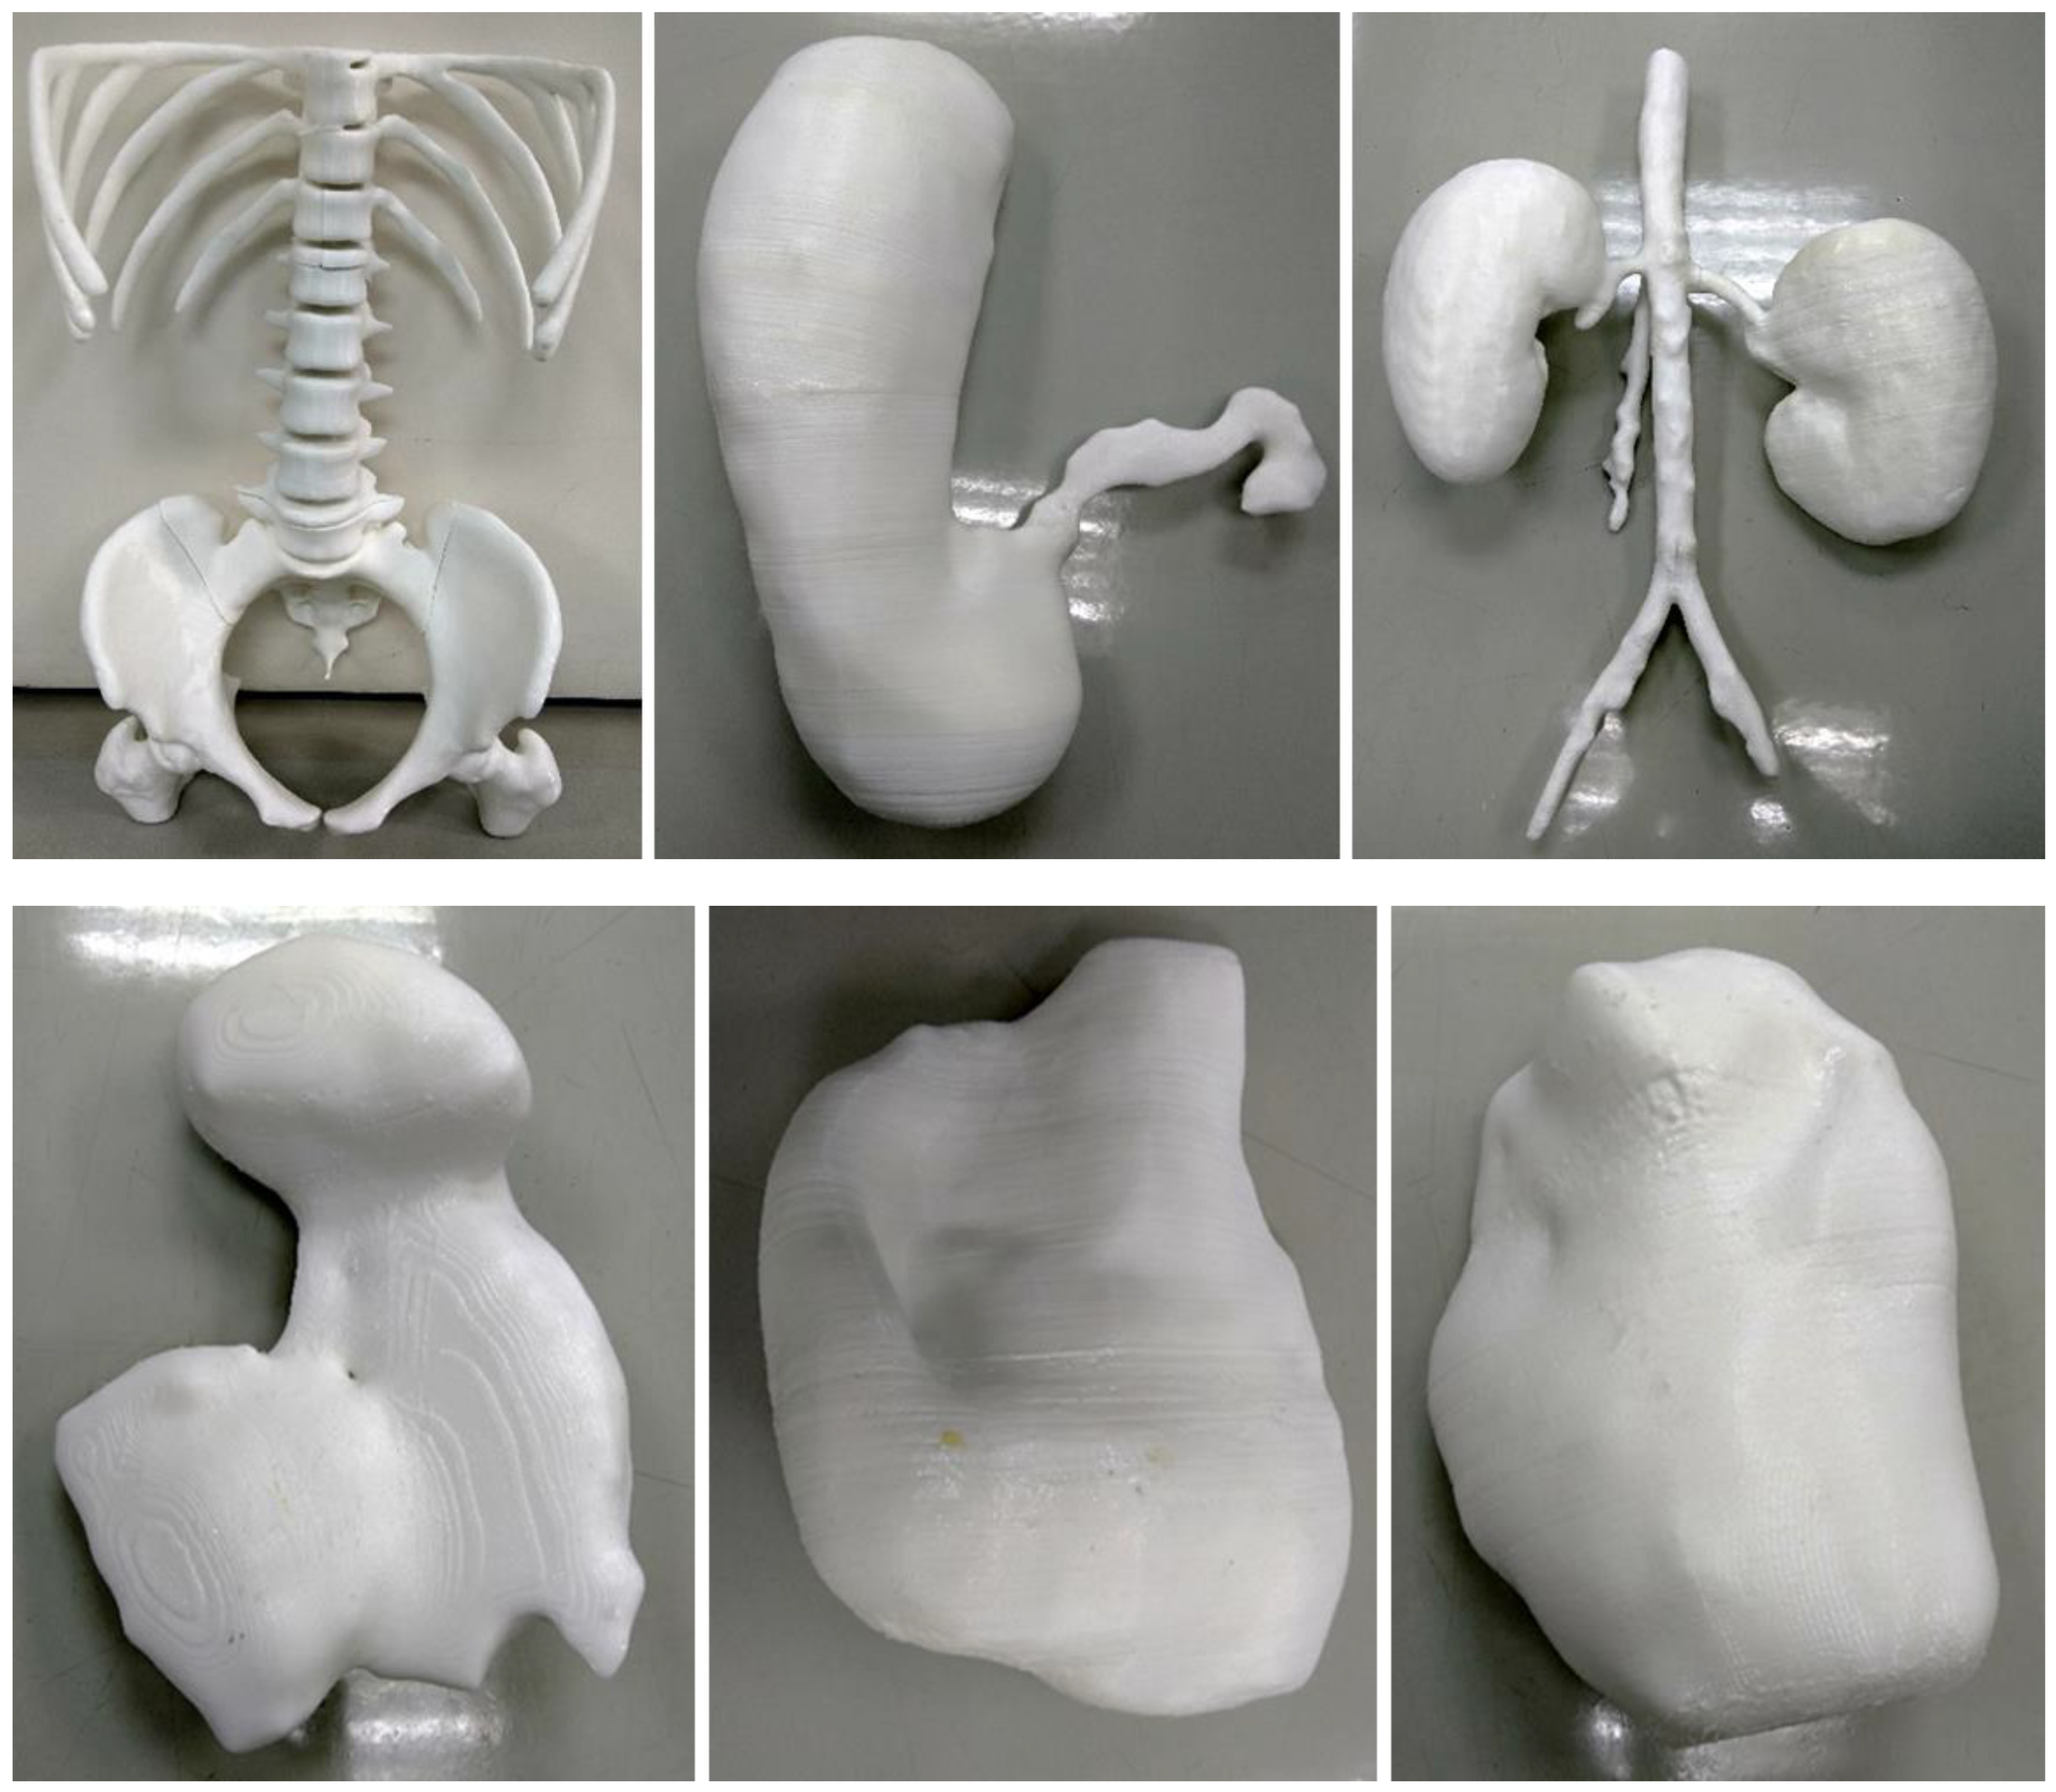

5.7. 3D-Printed Models of Abdominal and Pelvic Organs

- Etherton, D.; Tee, L.; Tillett, C.; Wong, Y.H.; Yeong, C.H.; Sun, Z. 3D visualization and 3D printing in abnormal gastrointestinal system manifestations of situs ambiguus. Quant. Imaging Med. Surg. 2020, 10, 1877–1883. [Google Scholar] [CrossRef]

| Abdomen and pelvis | Stomach: 1 Kidneys: 1 Spleen: 1 Bladder: 1 Uterus: 1 Skeleton: 1 | CT | Multiple organs for a case of situs ambiguus | Printer: Skeleton was printed using Raise3D N2 Plus (Raise3D, USA) Other organs were printed using Ultimaker 2+ Extended (Ultimaker BV, Netherland) Material: Skeleton: PLA Other organs: TPU 95A Cost: USD 55 for skeleton and USD 75 for other organs | Skeleton was printed with a resolution of 12.5 μm for the x and y-axis planes and 10 μm for z-axis plane Other organs were printed at a resolution of 12.5 μm for the x, y and z-axis plane Time: Skeleton: ~250 h Other organs: ~250 h |